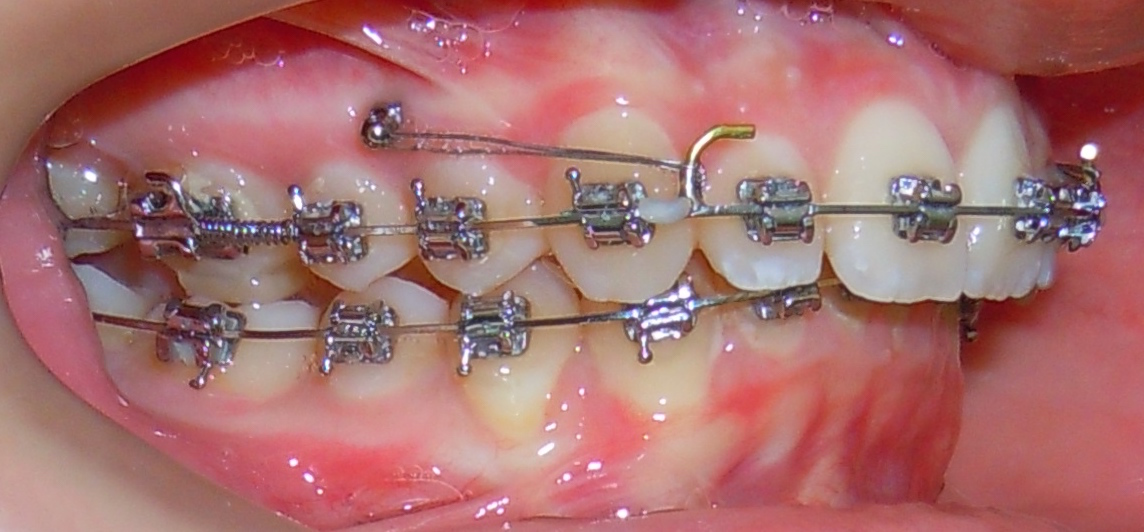

Mini-vis TAD pour distalisation des molaires

Distalisation des molaires

Molaires trop avancées créant de l'encombrement. Les TADs reculent les dents postérieures, créant de l'espace sans extractions.